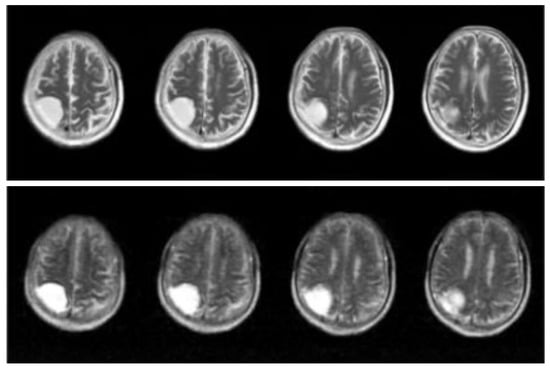

In Section 2.1, for MRI imaging technology, we introduce the advantages. However, MRI scanners rely on complex superconducting electromagnets and excellent electronic equipment for imaging, which leads to high cost, a large area of site occupancy, and demanding imaging site conditions. Therefore, people have begun to promote the development of low-cost MRI technology with ultralow field (ULF) intensity for large-scale medical image detection [53,54], which leads the MRI images’ disadvantage in that most clinical images are lost to computers [55]. Figure 1, Figure 2 and Figure 3 show the differences between T1-weighted images, T2-weighted images, and FLAIR-weighted images based on a high magnetic field, standard MRI images, and an ultralow field MRI, respectively. It can be seen from the comparison that these ultralow field MRI images have low brightness, poor contrast, no obvious details, and considerable noise, which is not convenient for computer and doctor detection.

Figure 3.

The top image is taken from the T2W strong magnetic field, and the bottom image is taken from the T2W weak magnetic field in the same position from left to right.